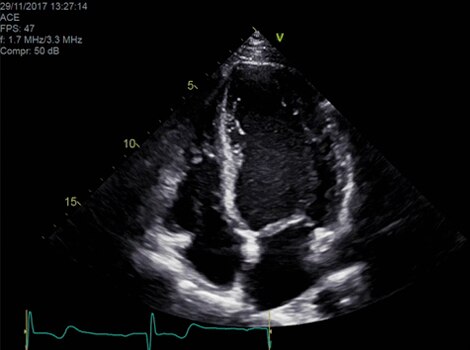

VividTM Family Cardiac Ultrasound Automated Function Imaging (AFI)

Assess left ventricular function and cardiac performance with clarity, improving clinical confidence.

Vivid™ Family Cardiac Ultrasound Automated Function Imaging (AFI)

Vivid™ Family Cardiac Ultrasound with Auto EF